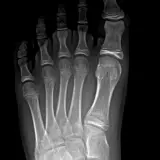

Over 2,100 interactive radiology cases, curated by radiologists for your level of training. Scroll, window, and view cases full screen — just like on PACS. Click linked findings in each writeup to jump straight to them on the image. Cases include sample reports, a focused discussion section, original illustrations, and videos.

Casos totalmente interativos com as ferramentas que você espera em um PACS — rolagem, ajuste de janela, zoom, movimentação, medidas, ROIs e modo de tela cheia.

Casos Interativos

Role, movimente, ajuste janela e amplie como em uma estação PACS do trabalho